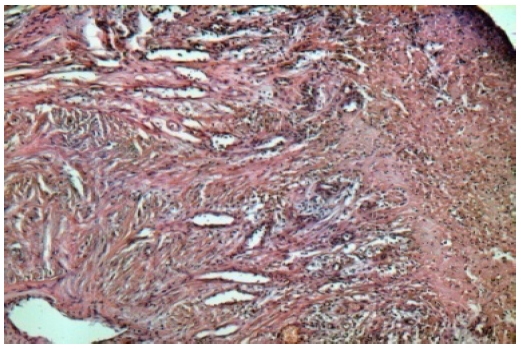

Положительная динамика течения раневого процесса в раннем послеоперационном периоде определялась и по данным морфологических результатов исследований, позволяющим говорить о выраженных пролиферативных процессах в ране на 5–7-е сутки, отсутствии воспалительных изменений на 10–12-е сутки (рис. 1, 2). Изучение показателей цитограммы также выявило раннюю смену некротического типа на благоприятный регенеративный тип к 7-м суткам после использования биоматериала «Коллост» по предложенному способу.

Рис. 1. Дно язвенного дефекта на 7-е сутки. Лейкоцитарная инфильтрация, детрит по поверхности язвы с активными признаками новообразования сосудов. Окраска гематоксилином и эозином. Увеличение 100 кр.

Рис. 2. Дно язвенного дефекта на 12-е сутки. Отсутствие лейкоцитарного вала, прорастание сосудов, коллагеногенез. Окраска гематоксилином и эозином. Увеличение 200 кр.

Таким образом, гистологическая картина из гнойно-некротических ран, в том числе с применением биоматериала «Коллост», дает возможность говорить о прогрессивной динамике регенерации тканей, выраженной в ангио- и коллагеногенезе.